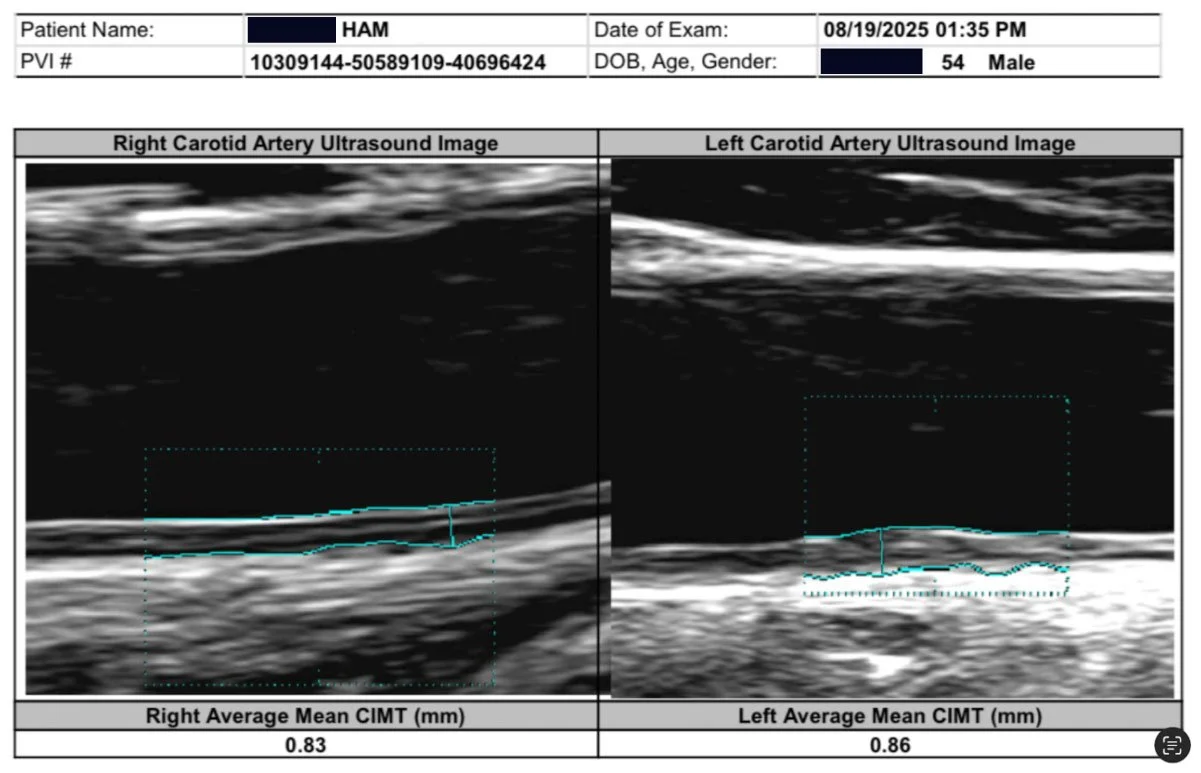

As you may know, I had bilateral plaque in the carotid arteries, now all gone. It seems almost miraculous, so I am studying the studies to understand the mechanism of how and what happened for such a remarkable result. I have reviewed the major carotid artery studies on exercise.

20 micrometres across 26 trials is a real effect, but a modest one. It is the average of every kind of exercise at every dose at every duration. My own carotid moved 700 micrometers in 90 days. 35 times the pooled effect. That gap is the question this whole series exists to answer.

• CIMT in the HIIT group: Decreased from 0.83 mm to 0.71 mm. A 14% absolute reduction in 12 weeks (p < 0.001)

• CIMT in controls: Unchanged. 0.84 mm at baseline, 0.85 mm at follow-up

This is 24 minutes of High Intensity and 18 minutes of Interval, so the total time is 42 minutes. At 3 times per week, that is 2 hours 6 minutes. I do 4x this amount. And I had 53% CIMT reduction in 12 weeks.

After thinking how I reversed my carotid plaque from May 9, 2025 (Started WFPB Esselstyn diet) to August 19, 2025, when my carotid ultrasound showed that all my plaque was gone and CIMT reduced 53%, I have been trying to understand the mechanism and biochemical pathways this occurred. I have been so focused on diet, that I wondered how much my 3000 km of cycling played a role. I did three Gran Fondo (120+ km) rides last year. Then after my September fondo, I basically stopped riding. My coronary plaque did not really reverse after that, although blood flow improved remarkably. So that has made me curious.

The carotid ultrasound at three months showed something I had hoped for but had not been certain enough to expect: both carotid arteries were completely clear. Not reduced. Clear. The plaques had resolved bilaterally in just three months. And the CIMT, the intima-media thickness that had read like an 85-year-old when I started, crossed into high-normal for age 55. By month ten, it was mid-normal. A 53% bilateral reduction in carotid arterial wall thickness, confirmed on imaging another three times afterwards, always improving.